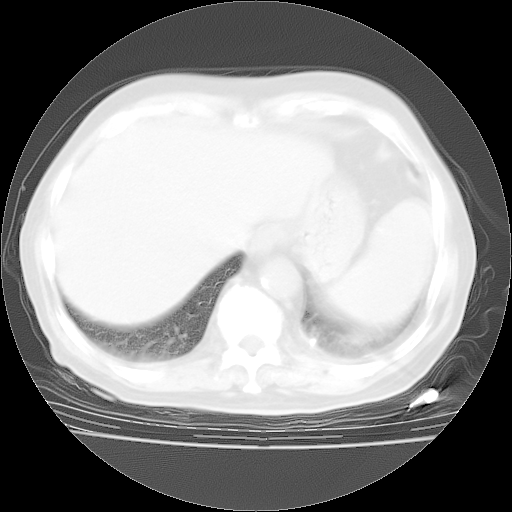

4月28日肺部CT

今请临免主任会诊后认为:4月14日胸部CT已有双下肺间质性改变。患者病情复发多系激素减量过快不正规所致。目前甲强龙80mg/日,一周后酌情开始减量,不易过快。环磷酰胺若已停用,暂不使用。他同意目前抗菌药物使用,但应考虑是否加用B-内酰胺类抗菌药物(中性细胞明显增高);2、结核复发目前依据不足;3、若免疫全套各项指标正常,考虑多系特发性肺间质炎可能大。4、加强支持,并注意保护胃黏膜。

今上午去请教了临免、呼吸主任:1、介绍病史和阅读系列胸部CT一致认为:患者肺结核不考虑,仍为肺间质纤维化,目前处于急性肺泡炎阶段。2、若仍发热,可将甲强龙增至:80mg Bid静滴,同时鉴于中性增高,合并细菌感染可能,继续左氧氟沙星治疗,再联用B-内酰胺抗菌药物,如头孢哌酮--舒巴坦;3、停用抗痨药;4、目前甲强龙每日剂量160mg ,体温正常后再酌情减量;目前暂不用免疫抑制剂;4、不建议使用免疫增强剂等;5、加强支持治疗,鼓励患者进食;5、注意随访肝、肾功及血常规情况;6、因患者目前激素用量较大,加用胃黏膜保护剂,防止消化道出血可能。